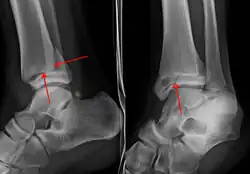

On X-rays, there can be a fracture of the medial malleolus, the lateral malleolus, or of the anterior/posterior margin of the distal tibia. [17] If both the lateral and medial malleoli are broken, this is called a bimalleolar fracture[18]. If the posterior malleolus is also fractured, this is called a trimalleolar fracture. [19]

A triplane fracture of the ankle as seen on plain X-ray -

A triplane fracture of the ankle as seen on CT -

A triplane fracture of the ankle as seen on CT